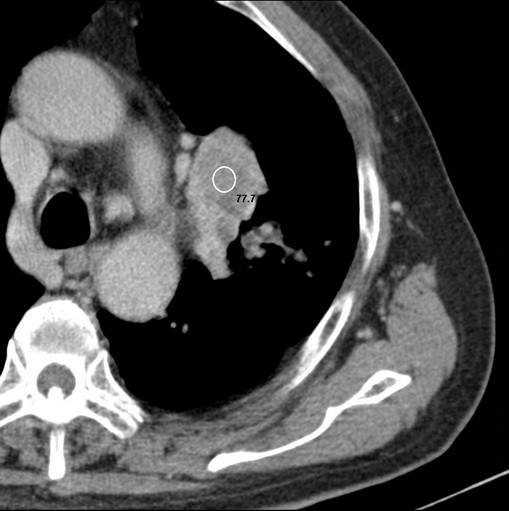

男性患者 81岁 咳嗽 咳痰 咯血

有强化 考虑肺癌肺门淋巴结转移

左肺中心型肺癌并:1.左肺阻塞性肺炎;2.纵隔淋巴结肿大;

强化较典型,左上肺癌并纵膈淋巴结转移;左上肺结核并空洞形成;胸膜增厚.

考虑左上肺癌并阻塞性肺炎,左肺转移、左肺门及纵隔淋巴结转移。

支持左侧中央型肺癌伴肺门及纵膈淋巴结转移。

肿块贴近左肺门,包绕左上肺动脉,形态不规则。肿块增强扫描中度强化。纵膈内主动脉弓左旁间隙、气管隆突前、下间隙见多枚淋巴结影。综上考虑左侧中央型肺癌可能性大。图片没有完整上传,尤其是左肺上叶支气管分支层面没有上传,因此不好判断是叶支气管中断还是段支气管中断。另外,下图红色部分所示是“黏液支气管征”吗?